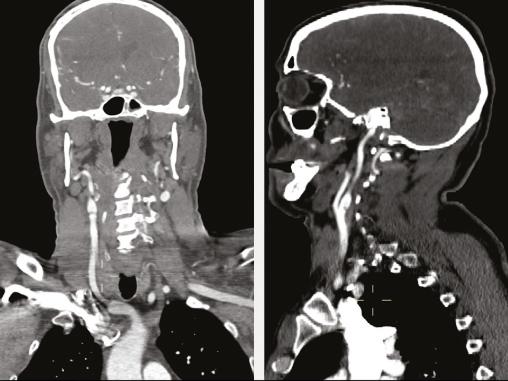

Cet homme de 41 ans, sans antécédent notable, était admis aux urgences pour une hémiplégie gauche d’apparition brutale (H3). Une angio-IRM cérébrale montrait un infarctus frontal et dans le territoire de l’artère sylvienne superficielle et profonde droit (fig. 1 ). Étant donné son jeune âge, un angioscanner des troncs supra-aortiques était réalisé, montrant une image d’éperon caractéristique de diaphragme bulbaire carotidien (fig. 2 ). Le patient était hospitalisé, mis sous traitement médical à base d’anticoagulant à dose préventive et d’antiagrégant plaquettaire en attendant la réalisation d’une artériographie avec mise en place d’un stent.